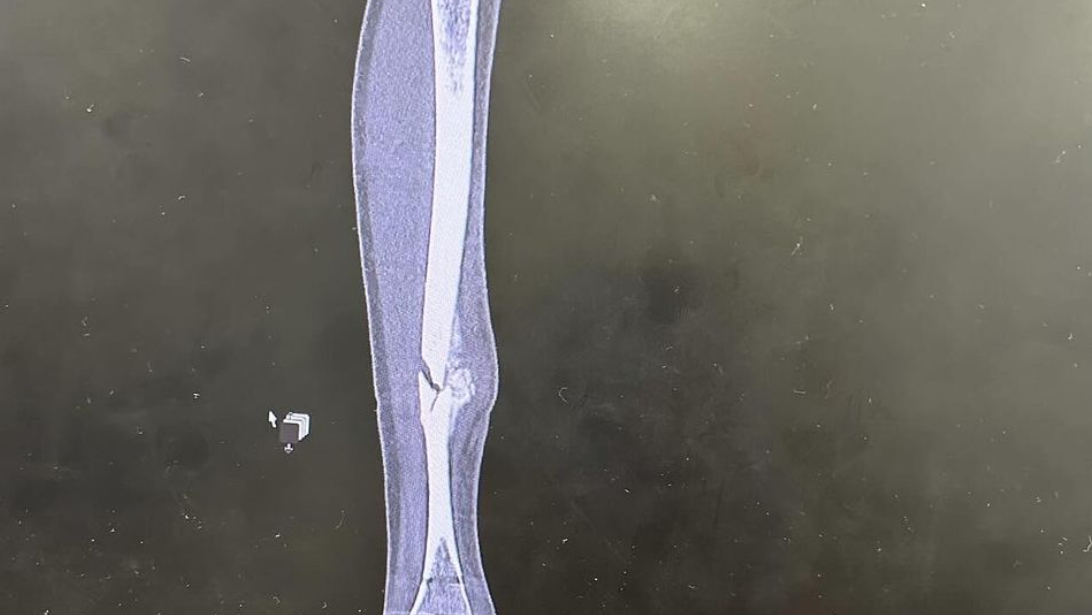

“Hasil pemindaian CT baru-baru ini dan saran dokter adalah untuk menghentikan semua latihan dan bersepeda sampai kaki saya pulih karena aktivitas lebih lanjut akan memperburuk situasi dan menghambat pemulihan saya.

“Sejak operasi, tulang-tulang saya belum pulih sama sekali, dan karena terlalu banyak bekerja pada cedera tersebut, saya memiliki kapalan berlebih di bagian luar kaki saya yang sedikit menggeser tulang dan pada dasarnya saya kembali ke titik awal.

Foto di bagian atas halaman ini diambil pada tanggal 13 September, saat Rogers pertama kali menerima saran dokter untuk berhenti.